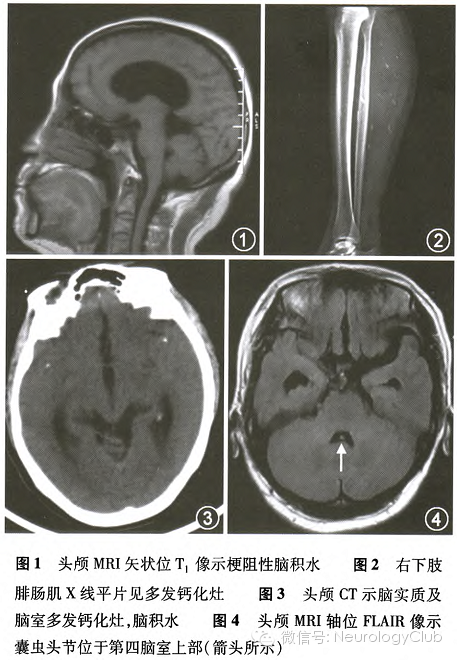

患者女,51岁,已婚,山东省沾化县人。主因“间断头晕3个月余,头痛1个月余”于2014年3月12日入住海军总医院神经内科。患者于2013年11月下旬无明显诱因出现头晕,恶心,不能转头,但站立时头晕无明显加重,按脑梗死治疗无好转。2014年2月2日患者出现间断右颅顶部胀痛,夜晚较重,服用尼美舒利可缓解。2014年2月17日出现走路不稳,伴踩棉花感。头颅MRI提示梗阻性脑积水(图1);胸部CT示双侧结节影,左侧钙化灶,双肺纹理增多。先后行4次腰椎穿刺(腰穿)脑脊液检查:压力均>330mmH20(1mmH2O=0.009 8kPa),白细胞(50-500)×10^6/L,葡萄糖1.12-1.15mmol/L,蛋白849-952mg/L。第1次腰穿后,患者行走不稳症状明显好转。既往史:30年前患结核性胸膜炎,胸腔积液,已治愈。当地医院按结核性脑膜炎予甘露醇及抗结核治疗(具体剂量及抗结核药物不详),患者症状缓解不明显。2014年3月6日行PET-CT示脑积水,颅内多发钙化灶;右侧甲状腺低密度影;双肺多发结节,考虑陈旧病变。为求进一步治疗于2014年3月12日入住海军总医院。全身体检:双乳腺可触到弥漫性增生结节。神经系统体检:记忆力减退;双侧视乳头水肿,边界欠清楚;双下肢肌力V-级。脑电图正常。乳腺彩色超声:右乳多发囊性结节,左乳实性结节。腹部B超提示脂肪肝。2014年3月13日行腰穿脑脊液检查:压力>330mmH20,蛋白1094mg/L,葡萄糖1.5mmol/L,白细胞50×10^6/L。甲状腺功能7项、肿瘤标志物(甲胎蛋白,CA125,CA19-9,癌胚抗原,CA15-3,鳞状细胞癌抗原,CYFR21-1,CA724,神经烯醇化酶)均阴性。结核分枝杆菌γ-干扰素释放试验(-)。

2014年3月17日患者行双侧腓肠肌、髋关节、颈部X线平片示腓肠肌、腹腔及颈部肌肉多发钙化灶(图2);头颅CT示颅内多发钙化灶,脑积水(图3)。2014年3月18日检查结果显示血及脑脊液特异性囊虫抗体(+)。遂明确诊断为脑室型脑囊虫病。给予吡喹酮150mg/kg(总量10500mg),吡喹酮从0.4g,2次/d开始,逐渐加量分7d服完总量。治疗第1天晚患者出现头痛加重及体温升高至39℃,第2天好转,遂加用甲强龙40mg/d,至吡喹酮治疗结束,患者未再有不适。2014年3月26日行腰穿脑脊液检查:压力270mmH2O,蛋白840mg/L,葡萄糖2.2mmoL/L,白细胞86×10^6/L。2014年7月30日电话随访,家属述患者在当地曾再次正规服用吡喹酮治疗1次,2014年7月29日复查头颅CT示脑积水明显好转,现病例仍在随访中。

戚晓昆主任医师 本例患者特点为以头晕起病,不敢转头,头晕症状直立时无明显加重,考虑为Bruns综合征。疾病呈反复发作,间有急性加重过程,考虑为急性颅内压增高。脑脊液检查提示炎症改变,但患者症状轻,无发热及感染证据,无消耗性表现,肿瘤标志物等检查未有明显异常。结合头颅影像学及病例特点,综合考虑患者为颅内感染,寄生虫不能除外,最终通过脑囊虫抗体检测得以确诊。本例患者为脑室型脑囊虫病,2012年周雁等也报告了类似病例。追问病史,患者表姐有脑囊虫病史,患者为农民,20余年前家里有养猪史,现否认疫源接触史。回顾患者头颅MRI显示第四脑室上部可见囊虫头节(图4),双侧腓肠肌可见经典的多发钙化灶,均支持该诊断。头颅CT检查对脑囊虫诊断极其关键,可发现脑实质、脑室内低密度囊虫影或高密度的囊虫钙化影。而该患者初始未行头颅CT检查,给诊断造成一定困难。